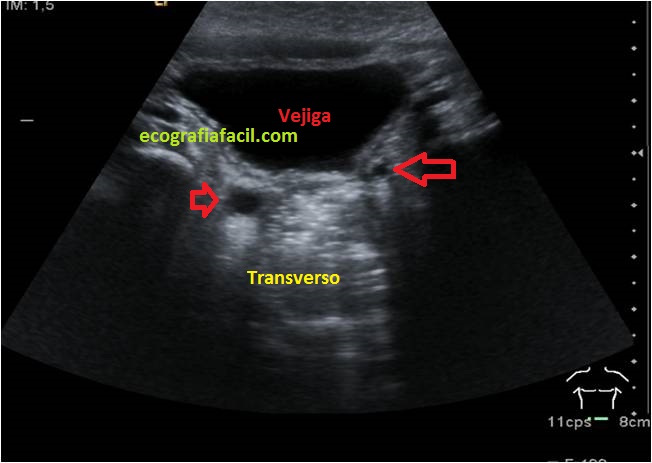

El Megauréter es la visualización de los Uréteres dilatados distalmente, que de forma habitual no tienen que ser vistos con ecografía, y además, se ven con un aumento de tamaño, anecoicos, redondos en transverso y alargados en longitudinal en las cercanías de su llegada a la vejiga…no es muy técnico lo que he contado, pero espero que lo hayáis entendido…¿no?, no te preocupes, mira las imágenes:

We have spoken in the 111 of the Pyelonephritis, that one of its causes could be the reflux, that is to say, as the content of the bladder can reach the Kidney and therefore if it is infected, affect the kidney … For this the malfunction of the ureters can be one of those causes … among others … in this link I leave you a complete review of those common pathologies of nephro-urological malformations in pediatric age, it is very interesting and I think your understanding is vital . The Megauréter is the visualization of the ureters that usually do not have to be seen with ultrasound, and in addition, they are seen with an increase in size, anechoic, round in transverse and elongated in longitudinal in the vicinity of their arrival to the bladder. ..it is not very technical what I have told, but I hope you have understood … no ?, do not worry, look at the images:

Megauréter bilateral, flechas rojas, anecoicos y redondos.

Bilateral megaureter (red arrows) anechoic and round.